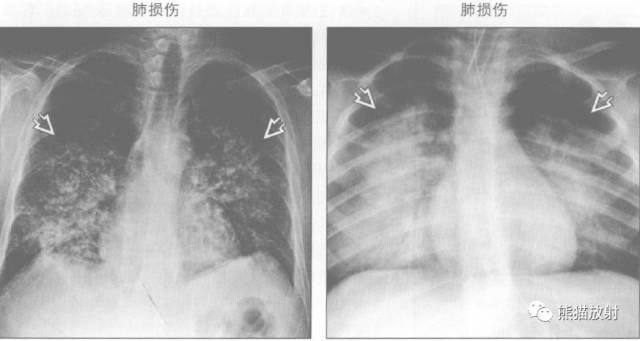

鉴别诊断

蝙蝠翼样肺部影可由以下原因引起:

↓ 卡氏肺囊虫肺炎